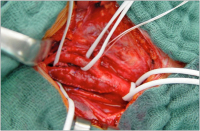

Karotisplaques

Abbildung 1: Karotisplaques